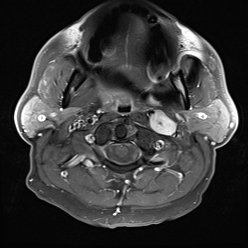

"CT and MRI Findings of Glomangiopericytoma in the Head and Neck: Case Series Study and Systematic Review" |

#HNrad | http://bit.ly/2sPvUYE pic.twitter.com/xjwyidHbAb